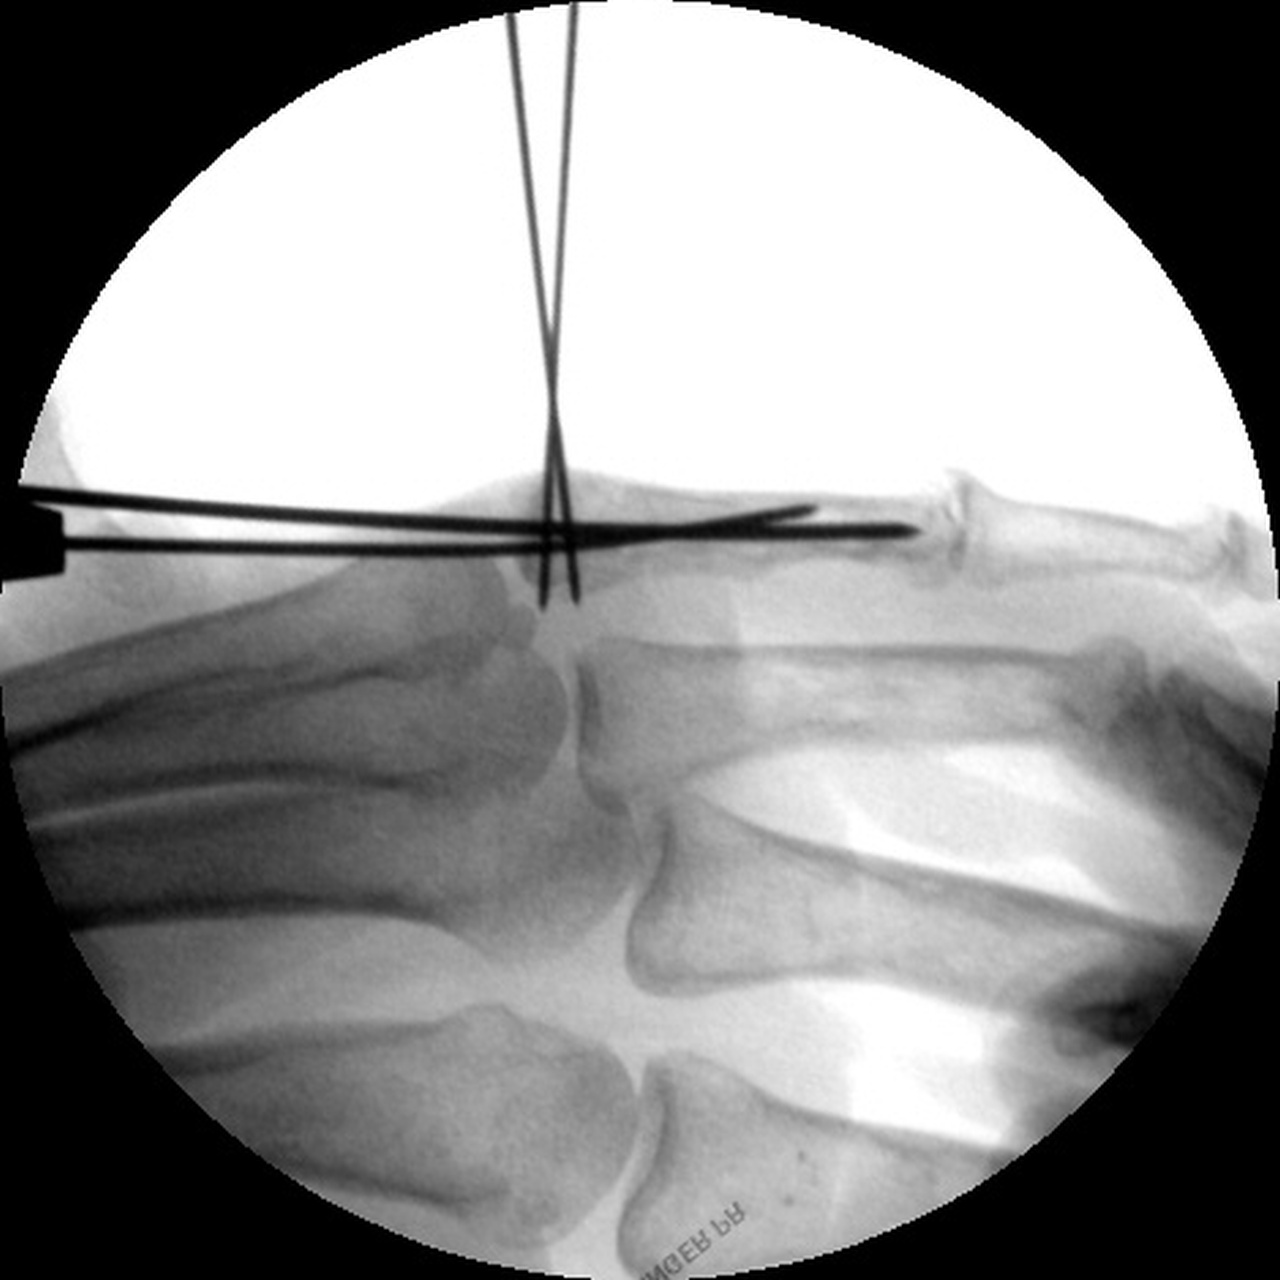

| Intraoperative

fluoroscopy. |

| Manipulation and closed reduction: |

| Percutaneous pins placed across the fracture line and also dorsal to palmar into the proximal fracture fragment. |